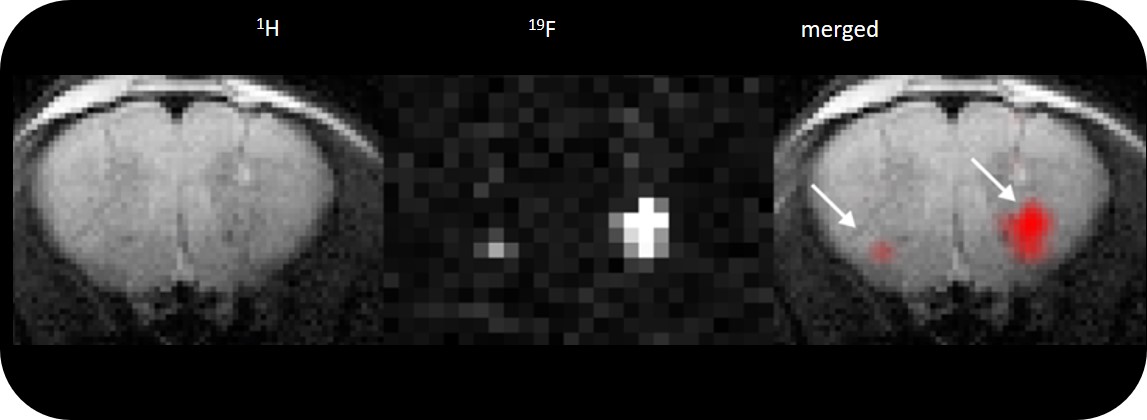

• Complete RF coil portfolio for mice and rats available, including coils for head, brain, cardiac, spine, body, multi-channel array coils with up to 8 channels, and x-nuclei

• MRI CryoProbe for exceptional increase in sensitivity

• Over 100 validated and ready to use in vivo protocols and scan programs for mice and rats

• MRI sequence portfolio of more than 1,000 sequence variations, including wireless cardiac imaging using navigator based IntraGate methods with cartesian or radial readout, as well as short echo time imaging, such as UTE and ZTE